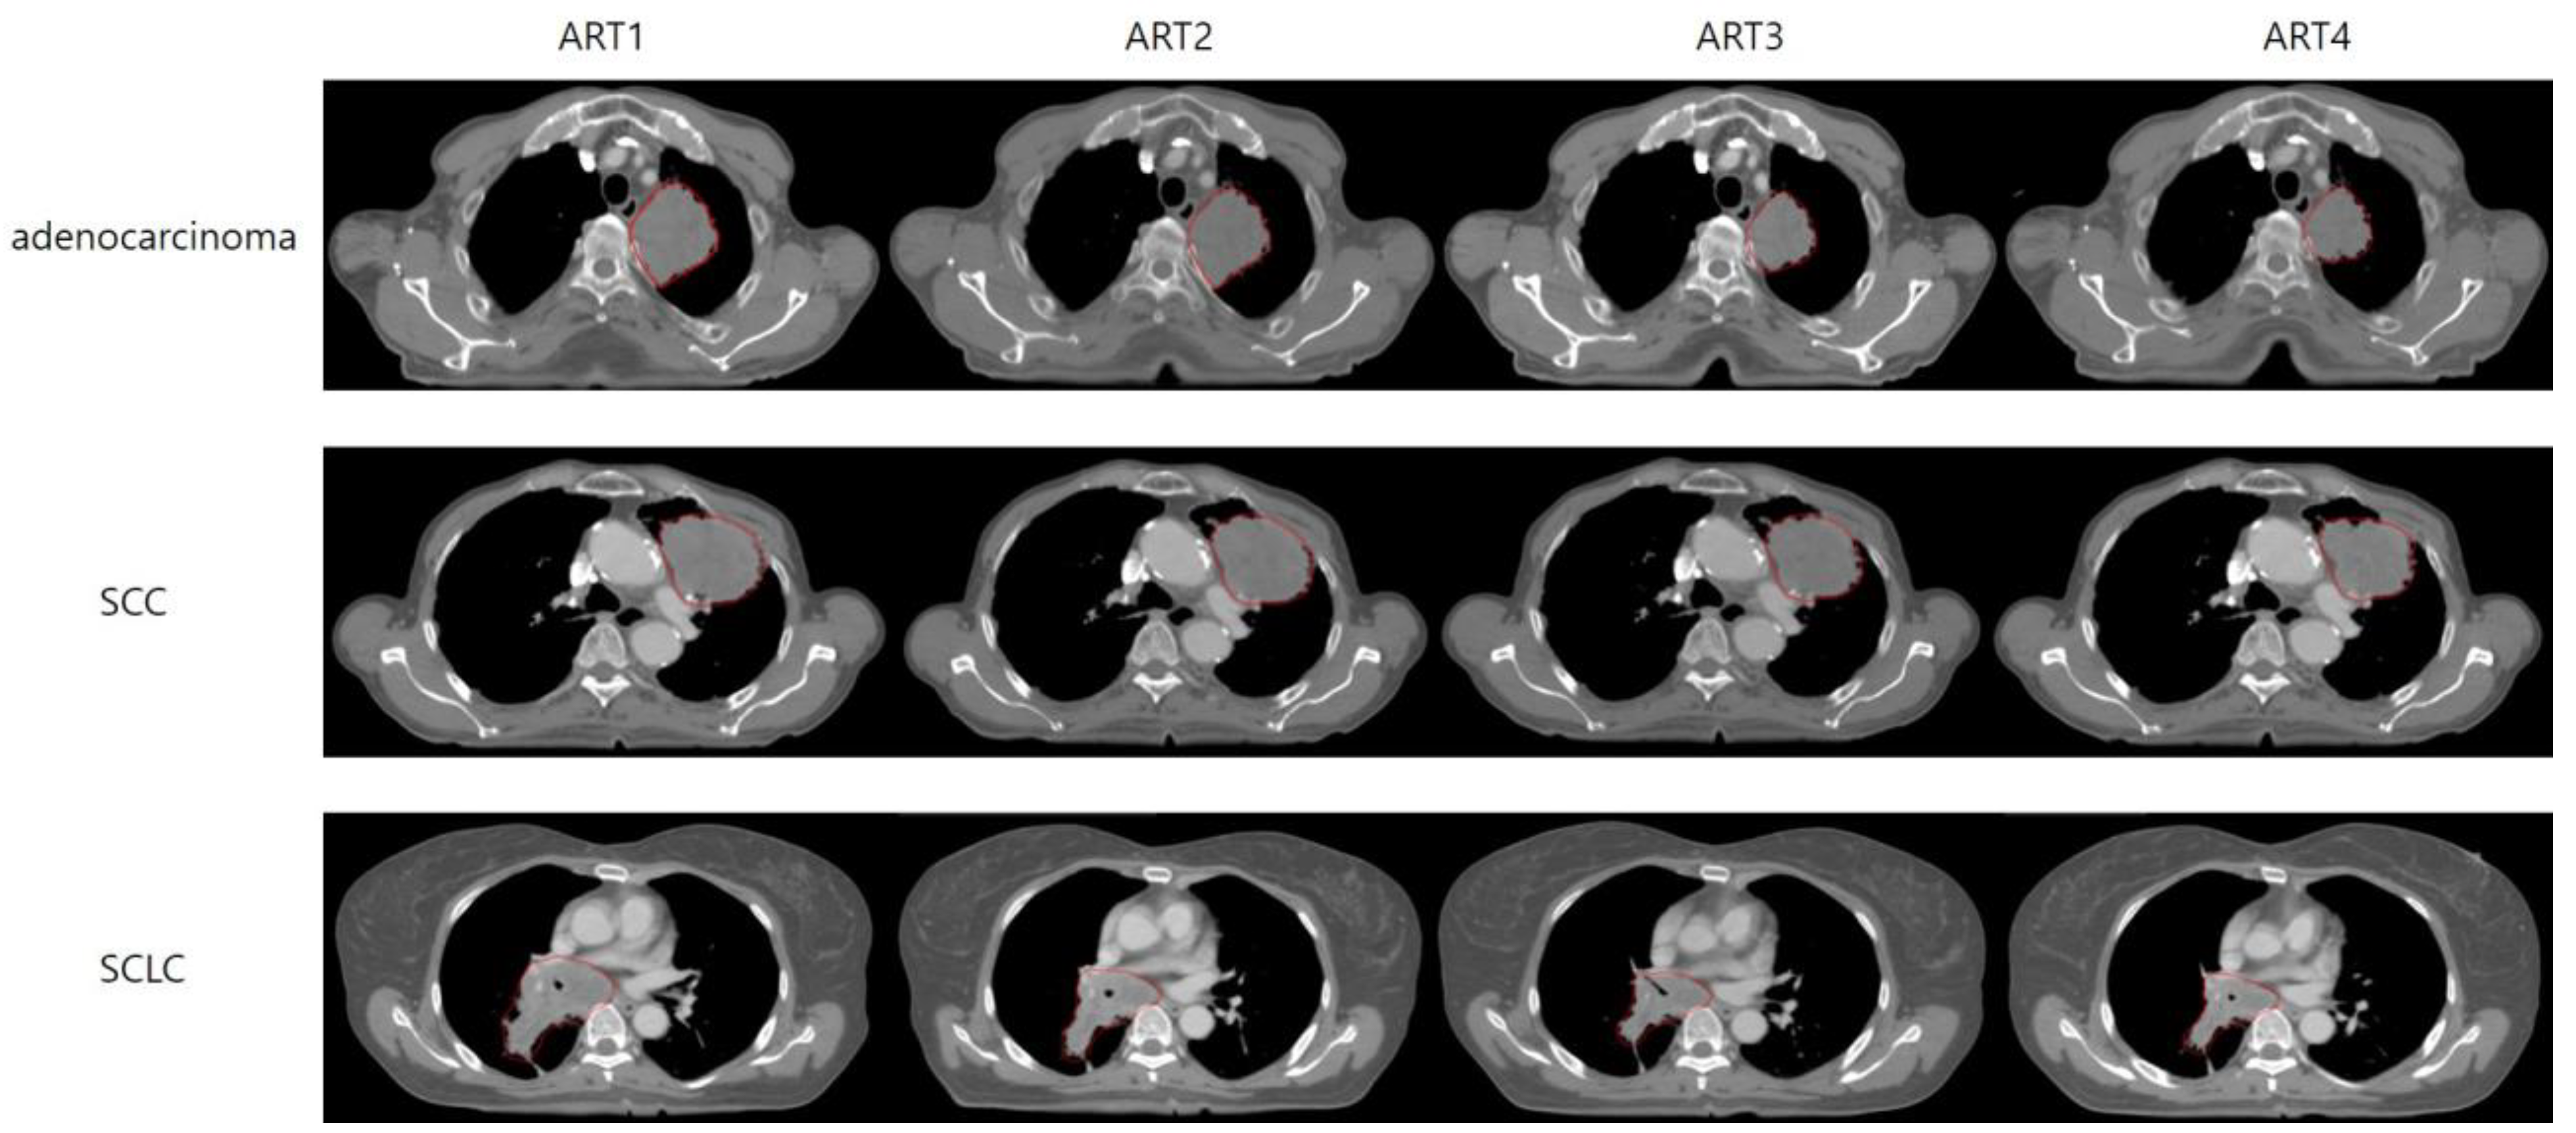

3.3. GTV Changes

3.3.1. Weekly Stepwise Tracking of GTV Changes: A Cumulative Comparison from the Start of Treatment

3.3.2. Weekly Interval Comparison of GTV Alterations